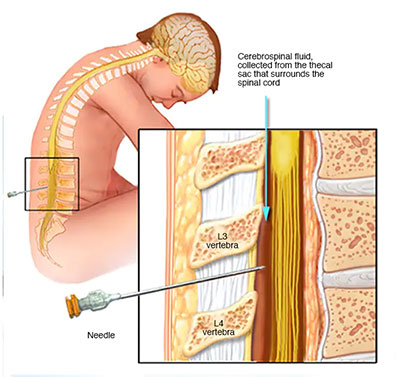

شیر نخاعی (پنچری کمر) :

که در آن یک نمونه کوچک از مایع مغزی نخاعی برای تجزیه و تحلیل آزمایشگاهی از کانال نخاع شما خارج می شود. این نمونه می تواند ناهنجاری هایی را در آنتی بادی های مرتبط با MS نشان دهد.

یک ضربه نخاعی همچنین می تواند به حذف عفونت و سایر شرایط با علائم مشابه اس ام کمک کند.